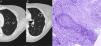

En un control radiológico de su enfermedad, y estando la paciente asintomática, se realizó una radiografía de tórax y una tomografía axial computarizada (TAC) de tórax que evidenciaron la presencia de 2 nódulos sólidos cavitados, uno de 15mm en el segmento apicoposterior del culmen (fig. 1A) y otro de 24mm en el segmento superior de la língula (fig. 1B).

TAC de tórax que muestra una lesión nodular cavitada en culmen (A) y otra en el segmento superior de la língula (B). C) Tinción de fibras elásticas para destacar la pared vascular arterial irregularmente destruida por el proceso inflamatorio. Se aprecia necrosis en el ángulo superior derecho. Orceina 200x.

Se decidió realizar biopsia pulmonar con tructut guiada por TAC de la lesión en língula. El estudio histopatológico mostró una lesión inflamatoria granulomatosa asociada a vasculitis compatible con granulomatosis con poliangitis (antes conocida como granulomatosis de Wegener) (fig. 1C).